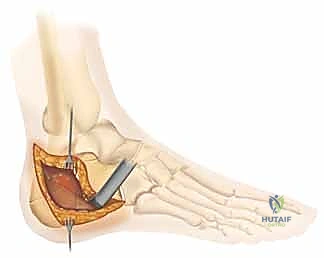

5. التثبيت النهائي باستخدام الشرائح والمسامير (Plating)

يتم وضع شريحة تيتانيوم (Titanium Plate) مصممة خصيصاً لتطابق الشكل التشريحي لعظم الكعب. يتم تثبيت هذه الشريحة بمسامير قوية لتوفير ثبات ميكانيكي صلب يسمح بالالتئام السليم ويمنع انهيار العظم مرة أخرى. في بعض الحالات التي يوجد فيها فراغ عظمي كبير، قد يستخدم الدكتور هطيف طعوماً عظمية (Bone Grafts) لملء الفراغ.